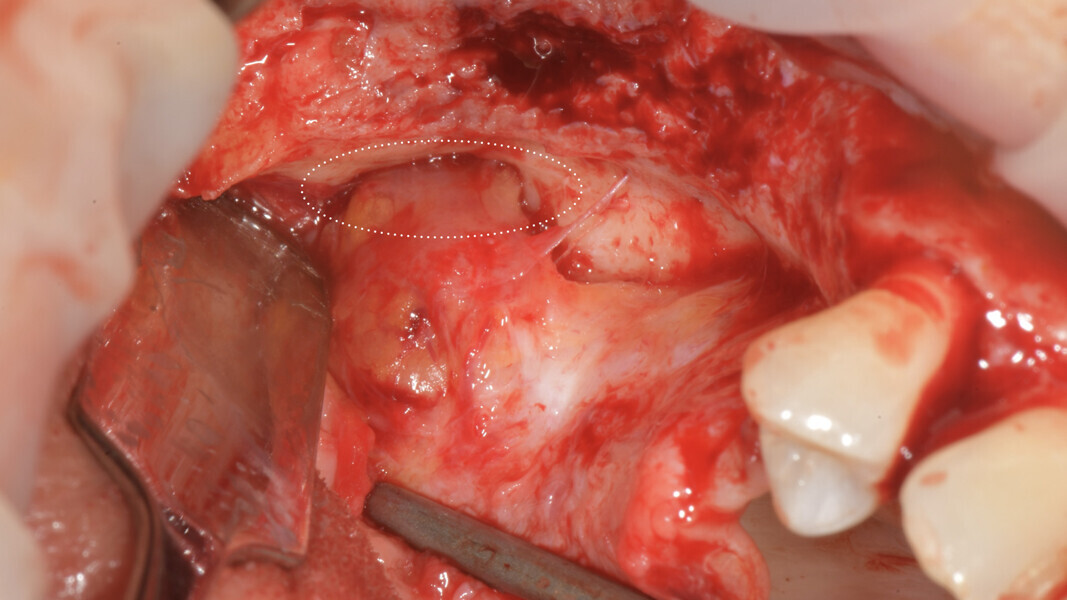

On the day of implant surgery, a para-crestal horizontal incision was made to expose the mesh and remove it, after the removal of the titanium screws and the new bone that had formed over the mesh (Figs. 25a & b, 26). Clinical examination showed complete regeneration of the vertical defect and the absence of pseudo-periosteum or thin pseudo-periosteum (< 1 mm), corresponding to the pseudo-periosteum Type 1 according to the Cucchi classification (Figs. 27 & 28).20